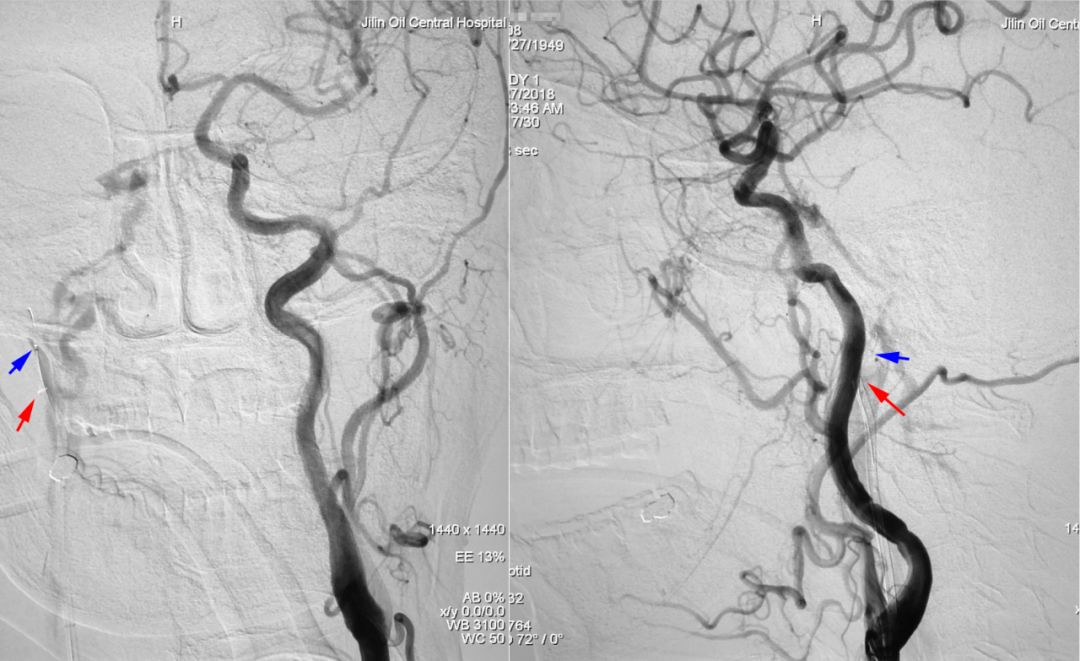

2018年10月12日行DSA示右侧海绵窦区硬脑膜动静脉瘘(Barrow D型),由双侧颈内、颈外动脉脑膜支供血,由右侧眼上静脉、岩下窦引流。

右侧颈总动脉正、侧位造影:

左侧颈总动脉正、侧位造影: